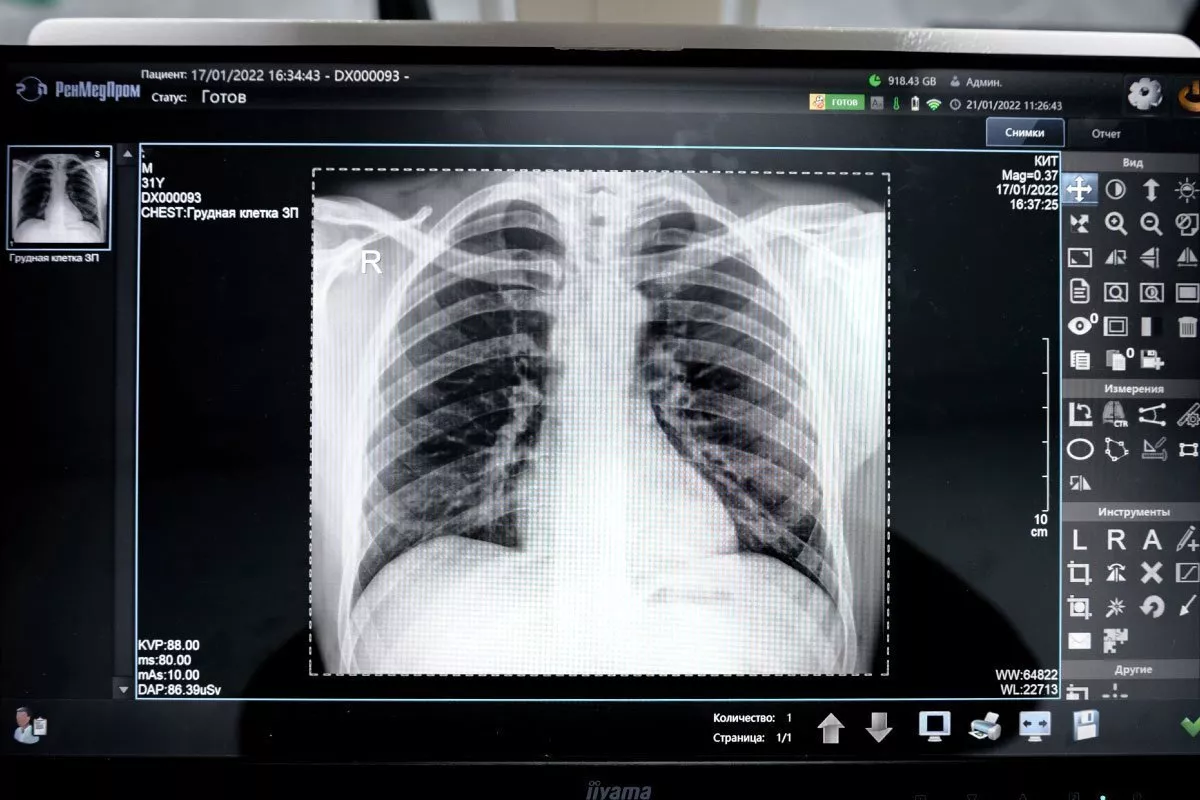

Рентген-аппарат «Дельта» — современная цифровая рентгенографическая система, предназначенная для быстрой и точной диагностики заболеваний костей, суставов и внутренних органов.

Аппарат позволяет получать высококачественные цифровые изображения сразу после экспозиции, что помогает врачу оперативно оценить состояние пациента и принять решение о дальнейшем лечении.

Рентген-аппарат «Дельта» — современная диагностическая система, предназначенная для проведения рентгенографических исследований костей, суставов, органов грудной клетки и других анатомических областей.

Аппарат использует цифровые технологии регистрации изображений, что обеспечивает высокую точность диагностики и позволяет получать качественные рентгеновские снимки практически сразу после проведения исследования.

• Высокое качество цифрового изображения — снимок формируется на экране сразу после исследования.

3. Получение изображения. Снимок отображается на мониторе врача.